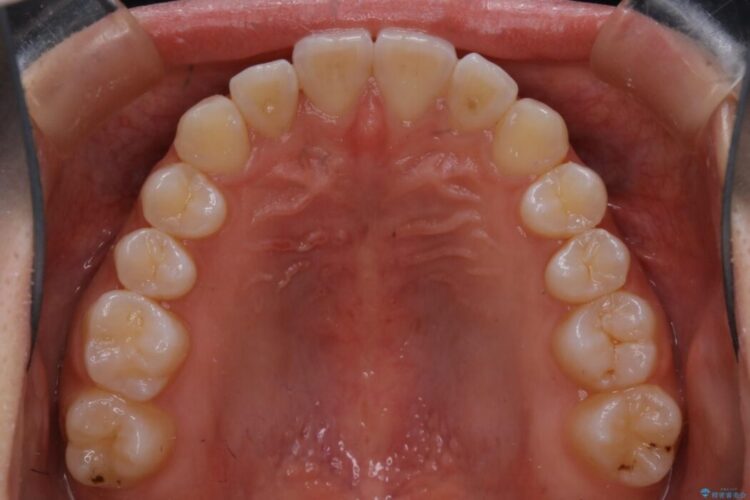

下の歯が上の歯より前に出ている受け口と前歯のガタガタ(叢生)について治療したいとのことで来院されました。

詳しく検査したところ、上顎の歯が舌側に倒れこんでしまっていることや歯列のガタガタなどにより口を閉じた時に上下の前歯の先端が接触してしまっていました。

よってまずは上顎の歯列を整えることから始め、前歯同士の衝突を改善してから、噛みこむ位置を本来あるべき後方へと調整することとしました。